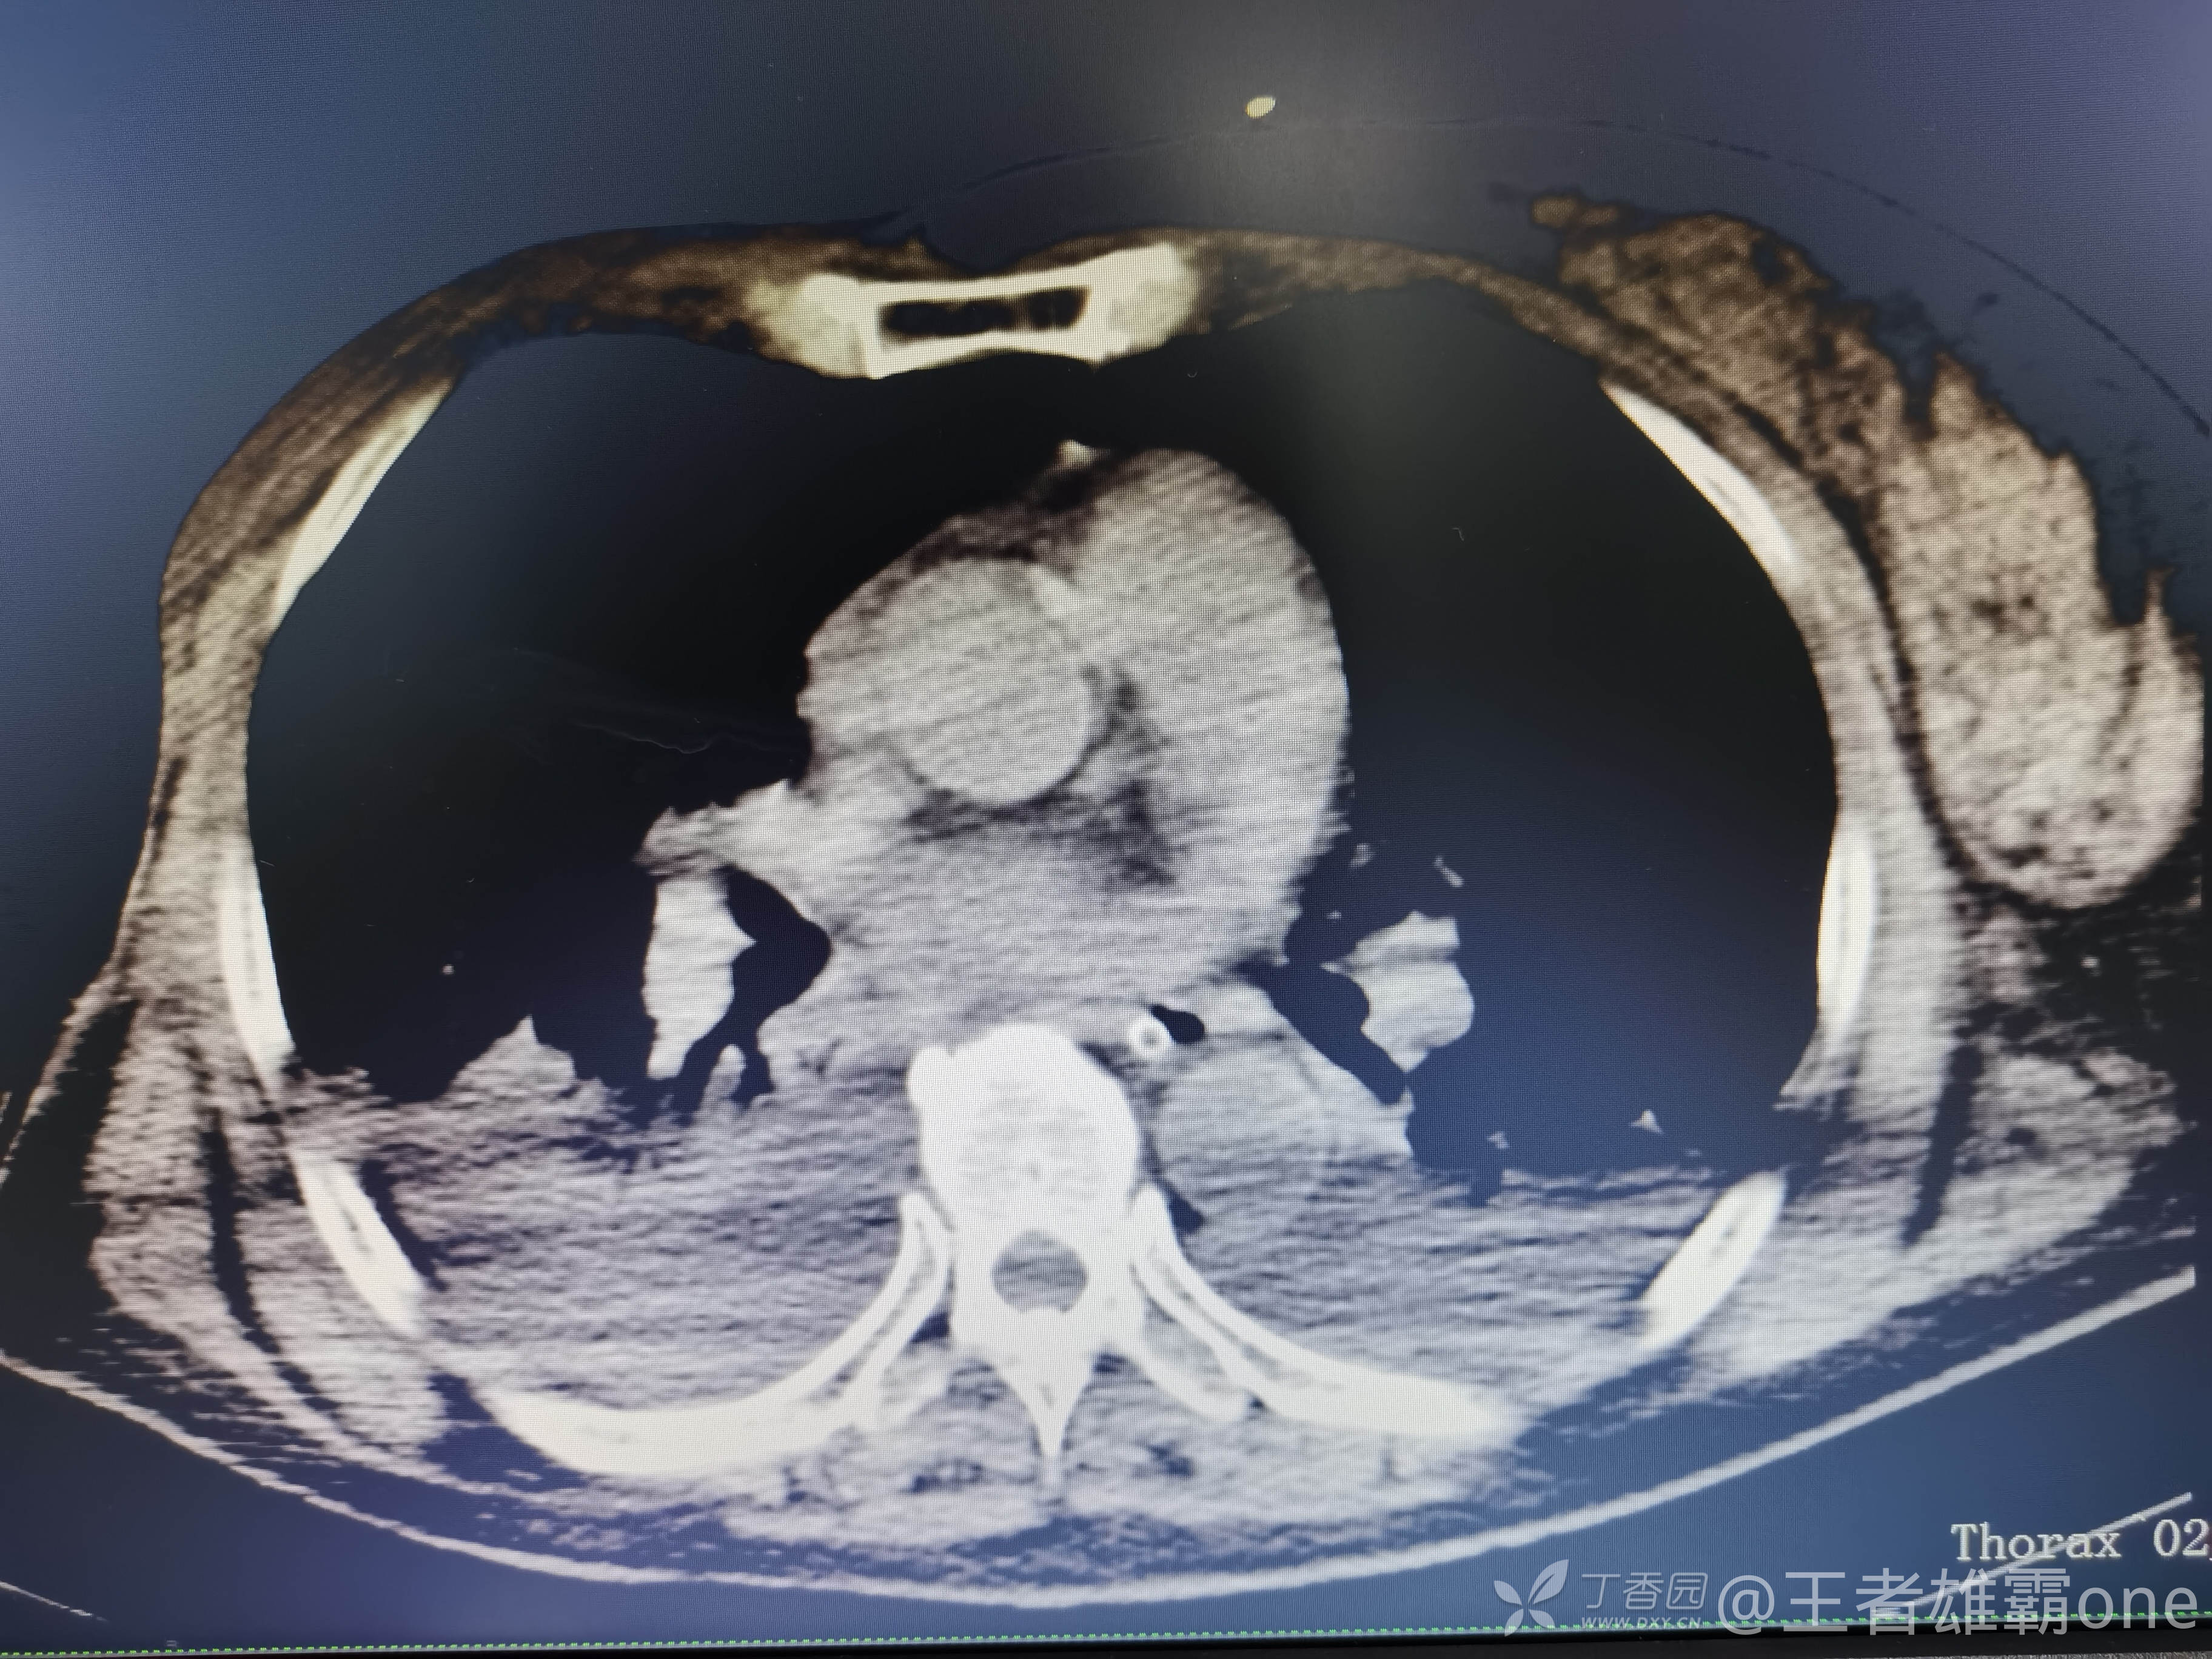

西门开心 推荐63岁女性,因车祸致短暂神志不清、多处疼痛4h入院。简单病史:伤后送至医院急诊就诊。完善头胸腹CT等检查,完善新冠核酸、血常规等化验。血常规提示血红蛋白62g/L。头颅CT提示未见明显外伤性改变。胸腹部CT视频见下:

早上复查血常规:血红蛋白100g/L,白细胞11.1×109/L,血小板29×109/L。凝血功能:APTT37.9s,纤维蛋白原3.01g/L,凝血酶时间18.6s,D二聚体21530ug/L。生化:白蛋白36.2g/L,胆红素指标正常,谷丙56U/L,总胆红素38mmol/L,直接胆红素12.1mmol/L,谷草57U/L,肌酐91.1ummol/L,尿素13.97mmol/L,超敏C反应蛋白142.1mg/L。降钙素原17.70ng/ml。脑钠肽前体2164pg/ml。复查胸部CT: